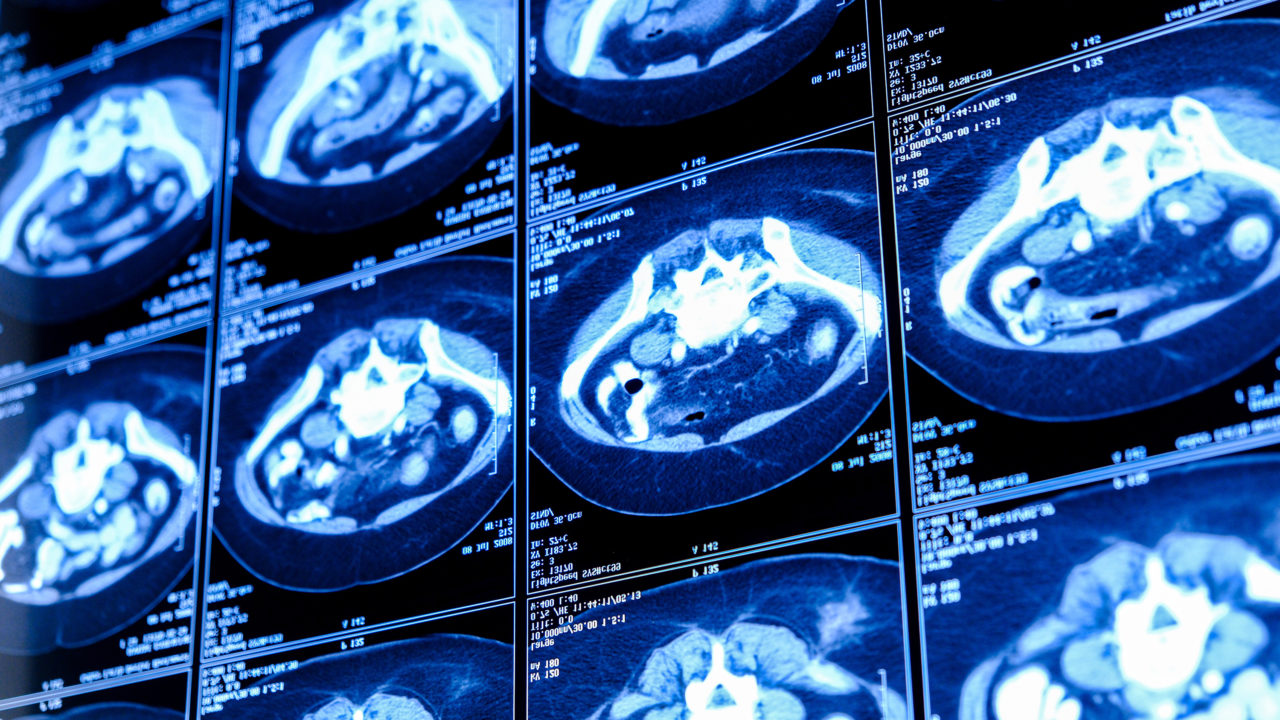

Hôpital Foch is pleased to introduce the creation of a new outpatient cancer care unit—an innovative initiative designed to transform the healthcare experience. This ambitious project aims to provide patients with high-quality care while improving their comfort and reducing the time spent in the hospital. With this new facility, Hôpital ...